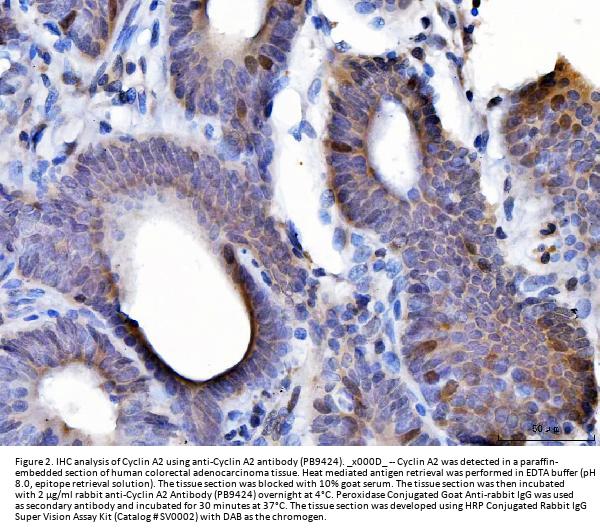

Immunohistochemistry (Paraffin-embedded Section), 2-5μg/ml, Human